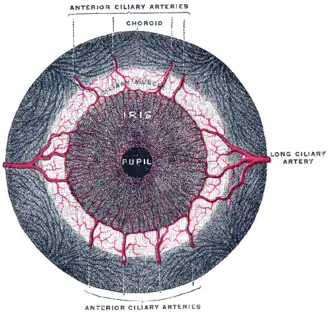

Iris, front view

Iris, front view -

Fluorescein angiograpy of the iris reveals a radial layout of blood vessels.

Fluorescein angiograpy of the iris reveals a radial layout of blood vessels.